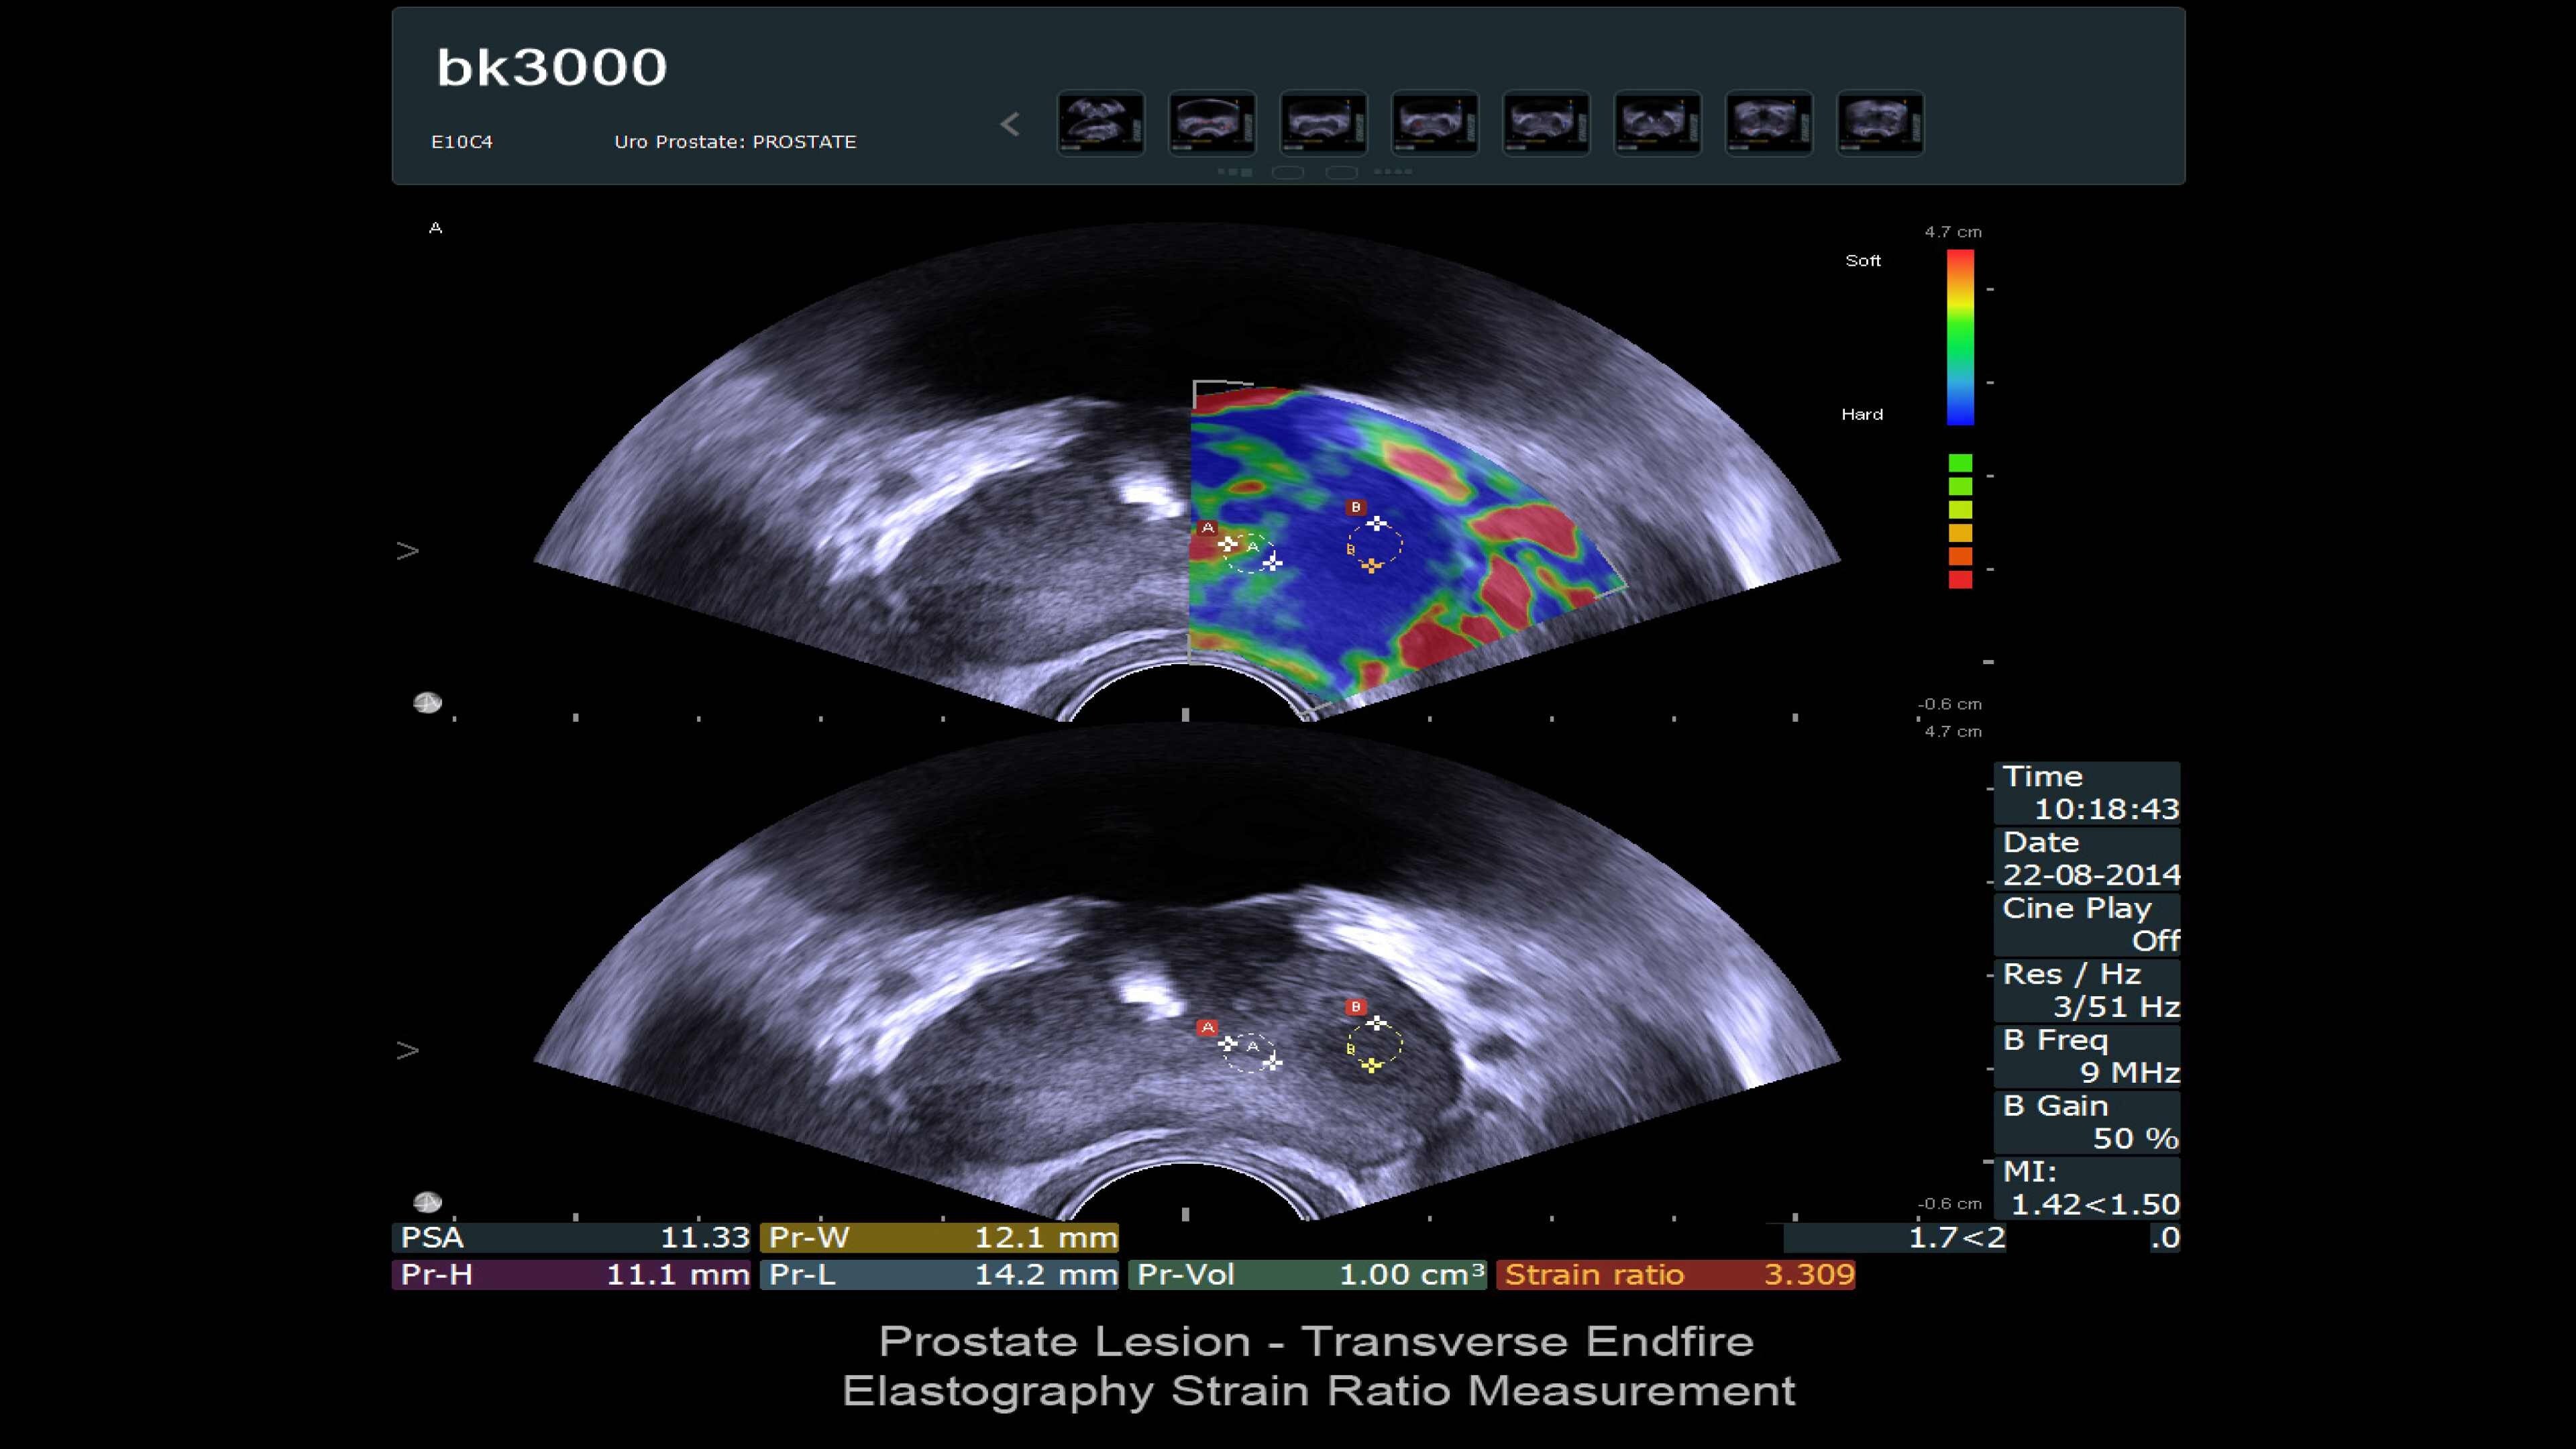

Ultra high-resolution imaging for Urology

The bk3000 ultrasound machine offers ultra high-resolution imaging for urology, including exceptional prostate, kidney, bladder, and testes imaging. It features real-time, high-definition prostate images, elastography for targeted biopsies, and a unique Triplane transducer for simultaneous biplane and endfire imaging. The system enhances lesion targeting with fusion-guided biopsies, combining MRI and ultrasound for precision prostate biopsies. Advanced imaging features and dedicated transducers improve visualization and treatment confidence during prostate interventions.